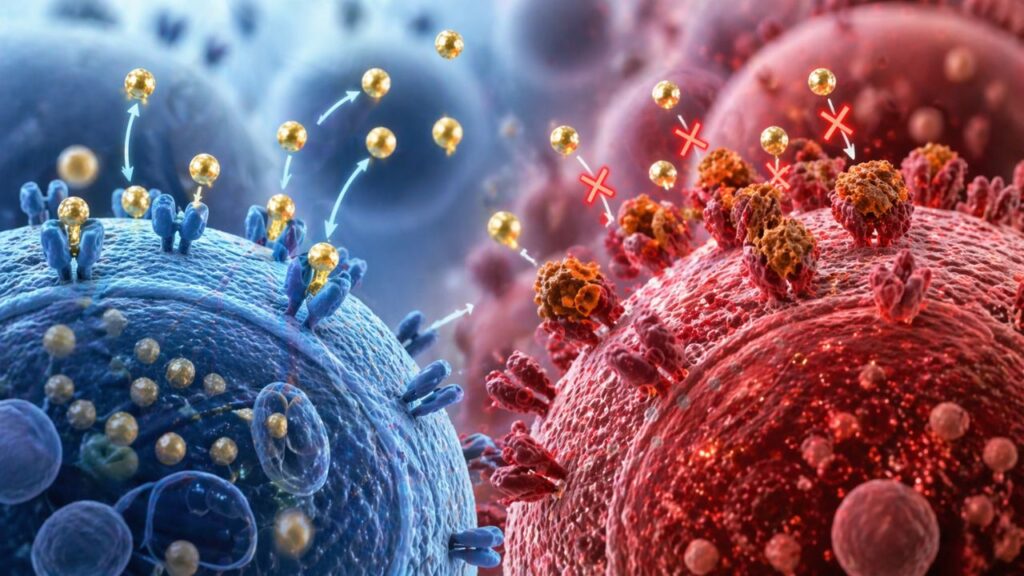

Esse processo inflamatório funciona como uma espécie de “interferência” no sistema celular. Os receptores que deveriam captar a insulina ficam bloqueados, dificultando a entrada da glicose nas células. Resultado, o açúcar se acumula no sangue, aumentando o risco de doenças metabólicas.

Os cientistas também observaram que a inflamação crônica está ligada a alterações no sistema imunológico e na comunicação entre as células. Esse desequilíbrio pode afetar órgãos importantes, como fígado e músculos, que são essenciais no controle da glicose.